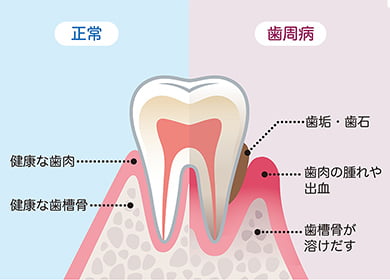

歯周病とは? What is Periodontitis?

歯周病は、歯周病菌が引き起こす歯周組織の感染症です。具体的には、細菌が歯と歯茎の境目に付着して歯肉の炎症を起こし、腫れや出血などが現れます。悪化すると歯と歯茎の溝がどんどん深くなっていき、歯を支えている歯槽骨まで溶かしてしまう怖い病気です。

歯周病で歯がぐらぐら揺れているのは、歯槽骨が溶けて歯が支えられなくなっているためです。 大切な歯を失ってしまう前に、ぜひご相談へいらしてください。